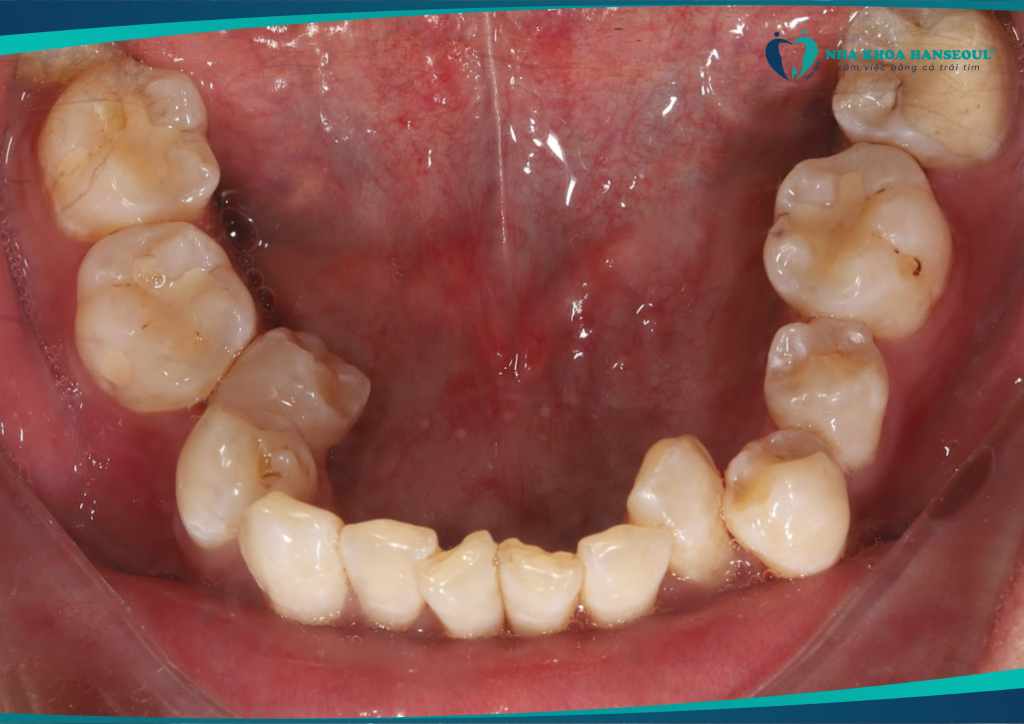

Khớp cắn ngược hạng III thay đổi ngoạn mục với Invisalign tại Hanseoul